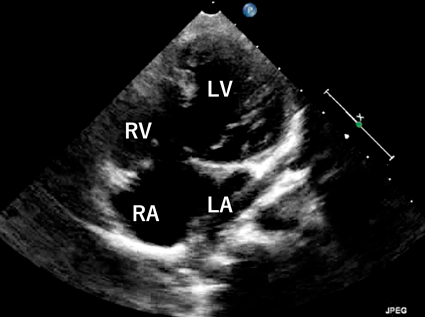

心エコー検査:中等度三尖弁閉鎖不全(TR)(Fig. 1A).

Fig. 1 Echocardiography and electrocardiogram

(A) The moderate tricuspid regurgitation was shown in the four chamber view. (B) Complete atrioventricular block was seen in 12 lead electrocardiogram. LA, left atrium; LV, left ventricle; RA, right atrium; RV, right ventricle; TR, tricuspid regurgitation.

心電図:完全房室ブロック(Fig. 1B).